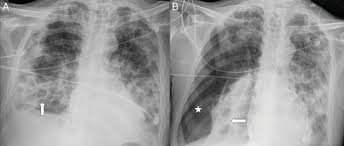

Pneumonia O Que E Causas Sintomas Tipos Tratamento Cura

Pneumonia O Que E Causas Sintomas Tipos Tratamento Cura from www.saudebemestar.pt